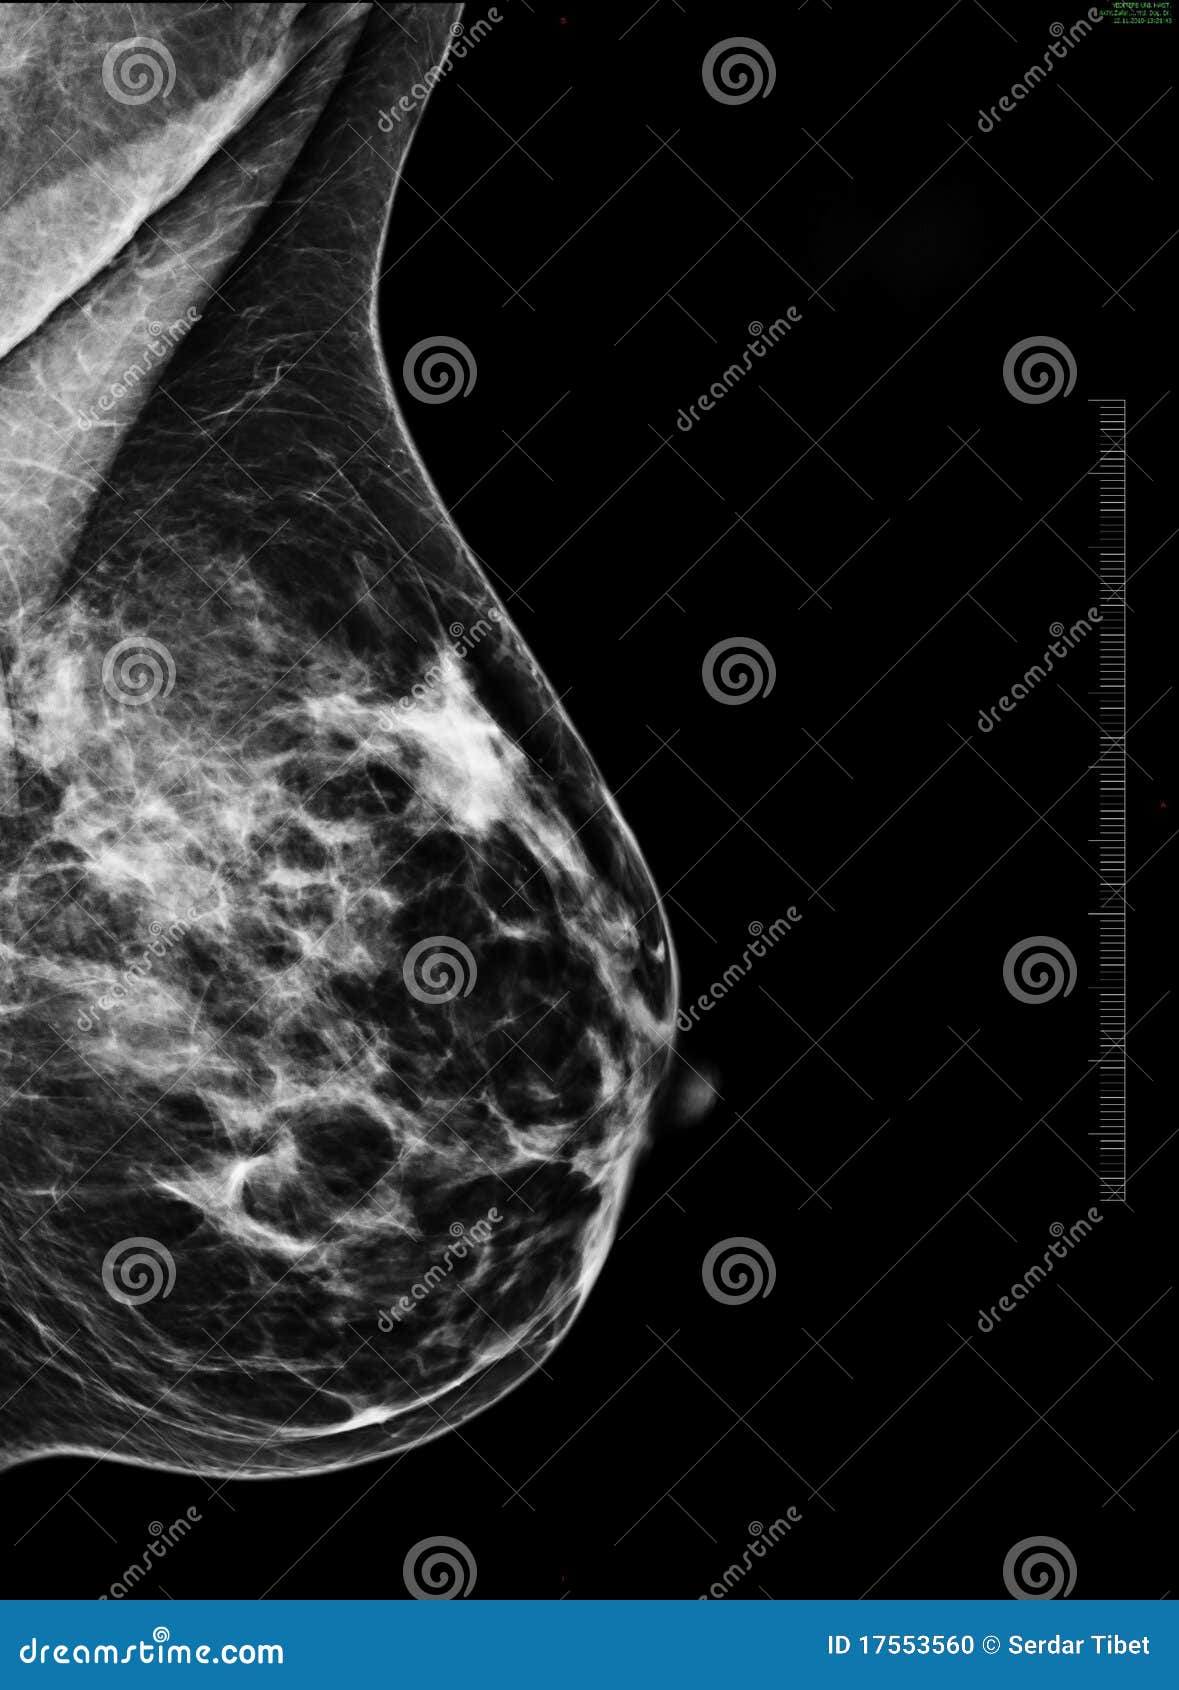

Фиброаденома молочной железы - доброкачественное образование, которое часто встречается у женщин. Оно может быть обнаружено при помощи различных методов диагностики, включая маммографию. Ниже представлены фотографии, помогающие понять, как выглядит данное заболевание.

Маммография и ее роль в диагностике фиброаденомы молочной железы

Маммография - это рентгенологическое исследование молочных желез. Оно позволяет выявить различные изменения в тканях, включая фиброаденому. На маммограммах можно увидеть структурные особенности опухоли и отследить ее динамику во времени.